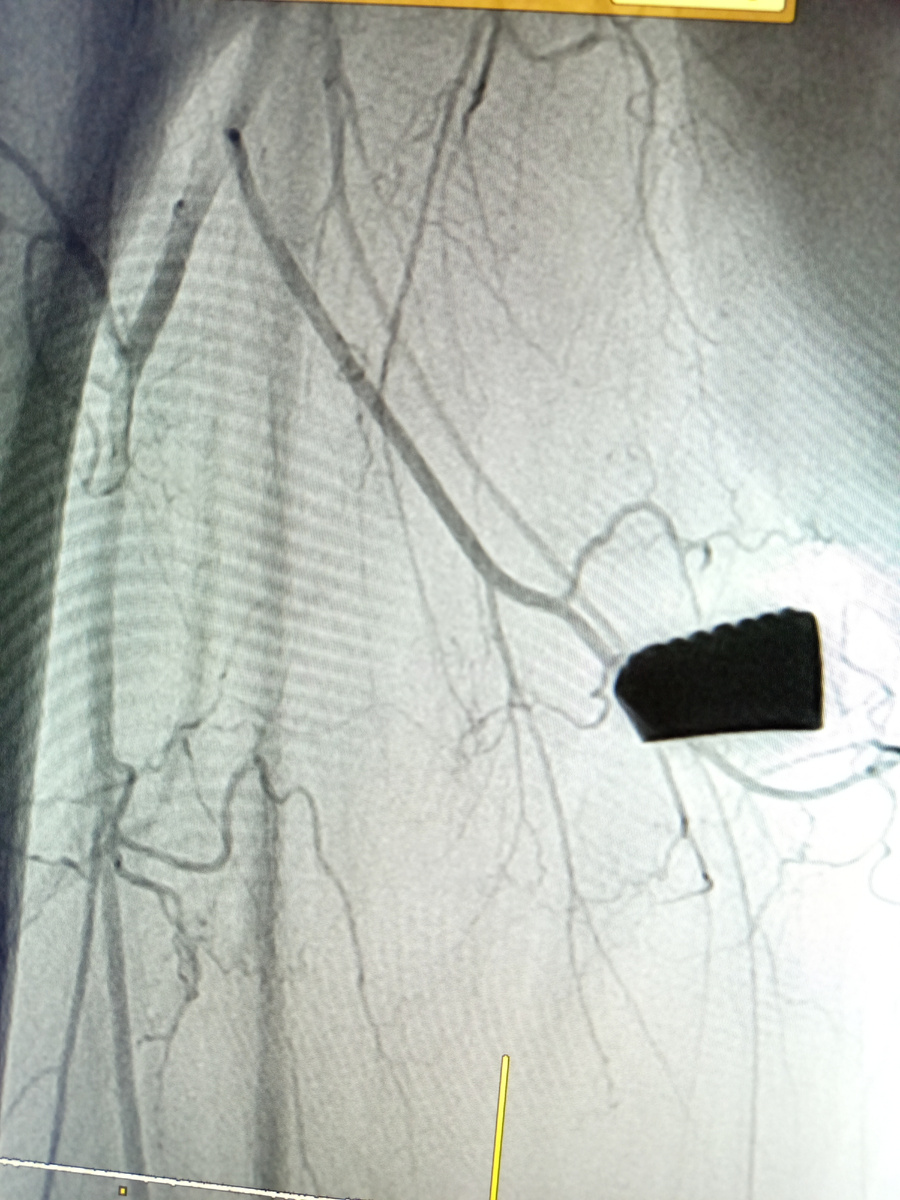

Артериография

Установили интродъюсер, завели катетер , по нему гидрофильный проводник, прокрасили сосуды.

Артерии проходимы, мелкие сосуды тоже видно.И видно , что место внедрения осколка плотно опутано сосудами

–Тут два варианта развития событий выходит, –объяснил наш врач пациенту , протранслировав ему само видео.–Либо вы решите , что осколок вам не мешает жить, и травматологи его не достают , либо нужно сделать эмболизацию.

–Мы остановим кровоток в том месте , где у вас осколок, после чего его извлекут без боязни повредить русло.